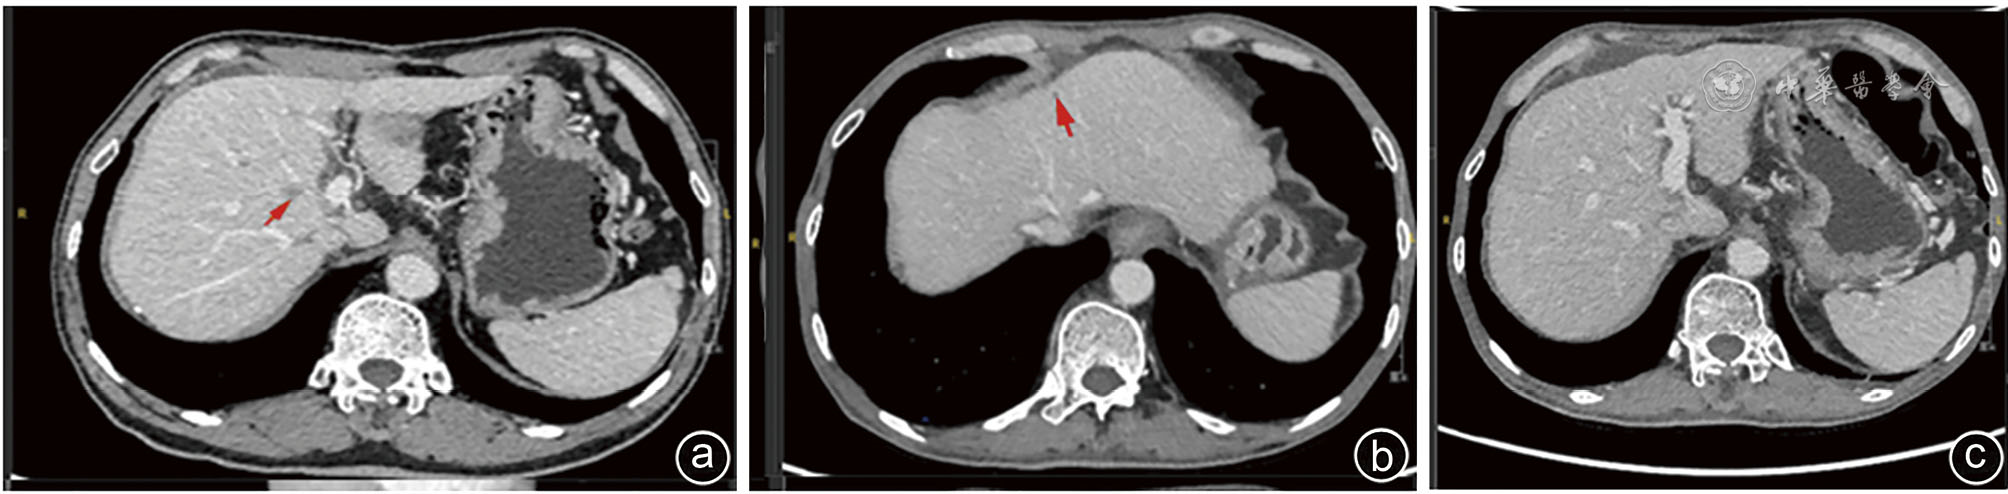

In this report, a 63-year-old male patient was admitted due to "dull pain in the right upper abdomen for 2 months". Imaging and pathological examination confirmed the diagnosis of synchronous hepatocellular carcinoma (CNLC Ⅰa stage) and duodenal papillary carcinoma (moderately-poorly differentiated adenocarcinoma complicated with signet ring cell carcinoma). The patient had a history of chronic hepatitis B. After Multidisciplinary team (MDT) consultation, laparoscopic local resection of segment 5 of the liver combined with pancreatoduodenectomy were performed to achieve R0 resection. Liver metastasis occurred 2 months after operation, and it was completely relieved after TACE, tirelizumab immunotherapy and FOLFOX4 chemotherapy. Postoperative survival time has exceeded 16 months. This case of synchronous double primary carcinoma of the liver and duodenal papilla is extremely rare, and it is likely to miss the diagnosis in clinical practice, suggesting that after the diagnosis of one type of malignant tumor, comprehensive evaluation is still needed to exclude other primary lesions. PET-CT shows important value in the early identification of such multiple primary cancers. Through multi-mode strategy of individualized comprehensive treatment and whole-course management, this patient achieved favorable tumor control effect, providing reference for clinical diagnosis and treatment of such rare cases.